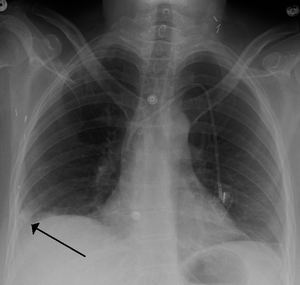

A Hampton hump in a person with a right lower lobe pulmonary embolism

يتم من خلال الأعراض المذكورة آنفاً وعن طريق الفحوصات الشعاعية كصورة الصدر الشعاعية, والتصوير الطبقي المحوري أو من خلال الصور النووية للرئتين، والفحوصات المخبرية الأخرى التي تساعد في التشخيص تعداد الدم الكامل وسرعة تجلط الدم، كما تجرى بعض التحاليل الدموية كإجراء وقائي ومنها فحص وظائف الكبد والكلى ومعدلات الشوارد وسرعة تسفل الدم. ومسح التهوية والتروية الرئوي هو شكل من التصوير الشعاعي التشخيصي هدفه تقييم التروية والتهوية في الرئتين ويستخدم في تشخيص الانصمام الرئوي. التصوير فوق الصوتي أو التخطيط التصواتي لأوعية الساق الدموية مهم لتقييم وجود أي خثار في أوردة الساق، يعد الإثبات بالإصابة بالخثار الوريدي العميق / جلطة الساق دليلاً هاماً على القابلية العالية للإصابة بالانصمام الرئوي. تخطيط القلب الكهربائي هو إجراء روتيني لأي مريض يأتي بألم في الصدر ويستخدم لإثبات أو نفي وجود احتشاء العضلة القلبية أو الذبحة الصدرية، كما لوحظ وجود 3 علامات كلاسيكية على تخطيط القلب الكهربائي في حالات الانصمام الرئوي وهي: موجة S كبيرة على القطب الأول I موجة Q كبيرة على القطب الثالث III موجة T معكوسة على القطب الثالث III ,7-8 ,3-5.[16]